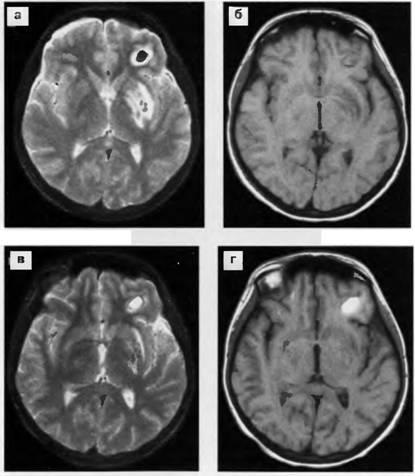

Ábra. 20. Dynamics zúzódás elváltozások (vérzéses impregnáló) CT. és - CT 15 nap traumás agysérülés után: több gócok növekvő sűrűségű (vérzés) és sűrűségét alacsonyan fekvő területeken lobnobazalnyh osztályok, több a jobb oldalon, és a tömörítés a jobb oldali kamrába; b -KT 27 nappal a sérülés után: szakaszai sűrűség csökkenése és izolált zsebek növekvő sűrűségű a fronto-bazális, inkább a jobb oldali; in - CT után 2,5 hónappal. sérülés után: a sűrűsége alacsonyan fekvő területeken a fronto-bazális aszimmetriája alsó szarvak az oldalsó agykamrák.

Ábra. 21. intracerebralis haematoma a bal parietális régióban. CT 3 nap (a), 7 napos (b) és 30 nap (c) traumás agysérülés után: fokozatos csökkentését a sűrűsége vérömleny, mivel a perifériás részek.

Ábra. 19. zúzódás gócok a jobb parietotemporalis és elhagyta az alagsorban (a típus protivoudara) területeken. CT (a, b) 8 órás traumás agysérülés után: kis zsebek sûrûsödések jobb temporo-bazális és a bal parietális területek a jobb oldalsó agykamra elhagyta, az elmozdulás a kamrai rendszer nem. MRI T2 (a) és T1 (g) módok: magas jel gócok a jobb temporo-bazális, a bal oldali temporális és parietális területeken.

Ábra. 18. zúzódás gócok a bazális halántéklebeny mindkét oldalán, és a frontális (többnyire jobb) egy gyermek 10 éves. CT (a, b, c) 3 órán traumás agysérülés után. vérömlenyek sűrűség növekszik, a periférián - alacsony sűrűségű terület.